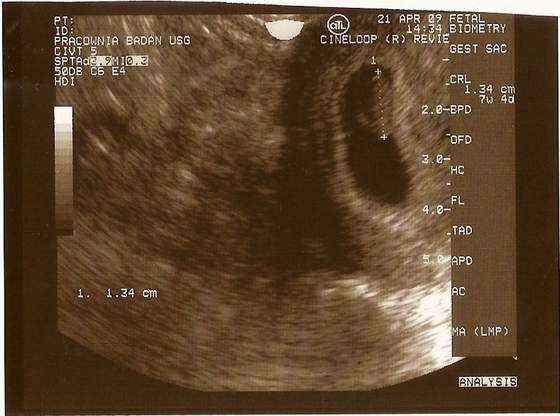

wczoraj wieczorem byłam u gina zrobił mi usg i wiecie co widziałam jak bije serduszko

nie mogłam w to uwierzyć.

Jestem teraz w 7 tygodniu i 4 dzień, a mój dzidziuś ma 1.34 cm

lekarz powiedział ze jest duzy ale nie mam sie czyma martwić bo jest wszystko w jak najlepszym porządku :-):-):-)